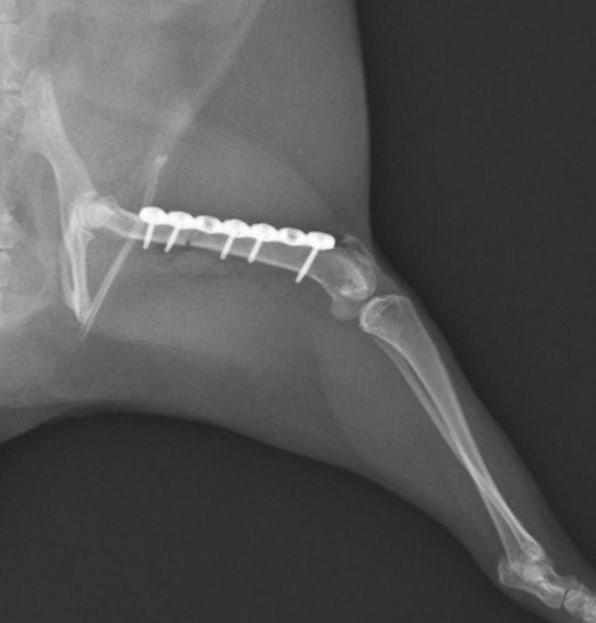

大腿骨骨折のフェレットちゃんの手術依頼でご紹介がありました。TAITAN1.2プレートを使用し無事歩けるようになりました。よかったね。